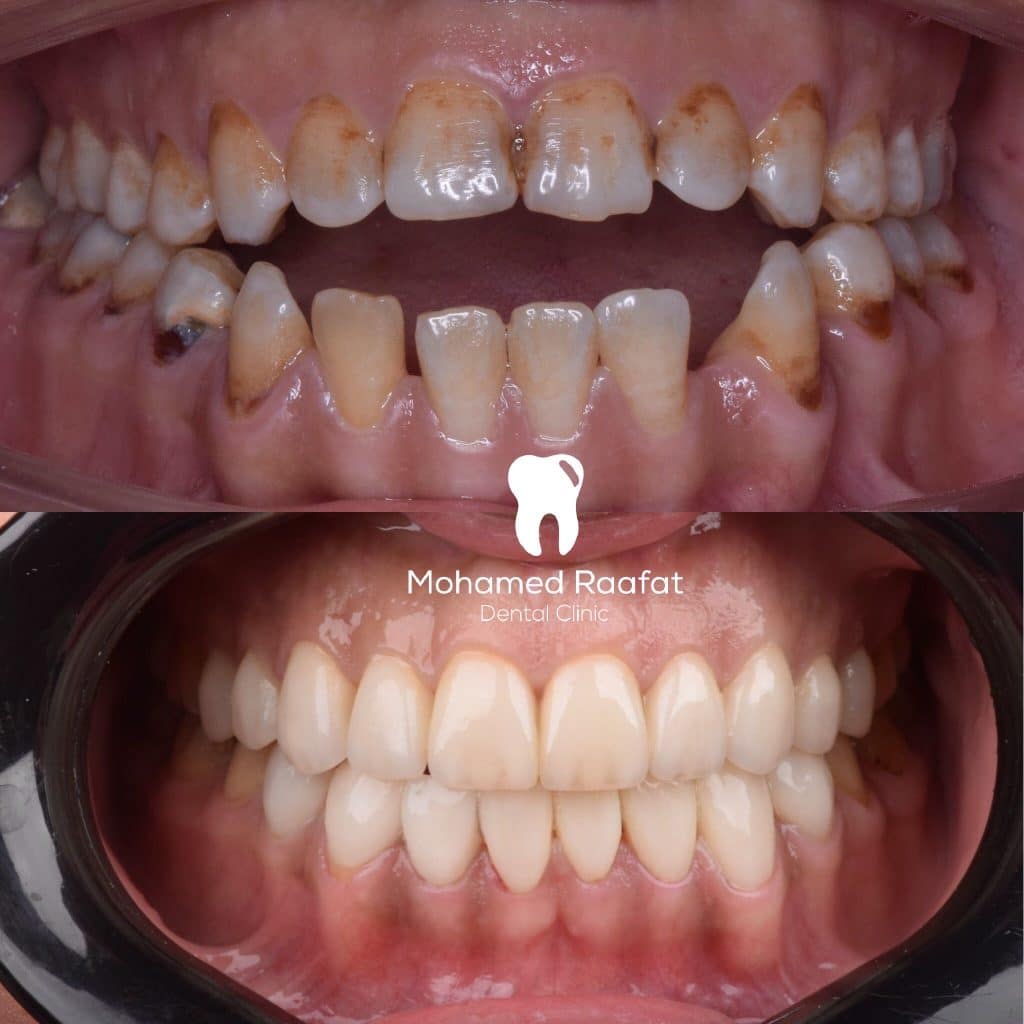

A 36 yrs old female patient presented with class lll incisor relation with anterior open bite (dental component) on skeletal 3 , proclined lower anterior and decreased incisal show ; that was complicated by generalized enamel hypoplasia and multiple caries spots on some of the teeth

After discussing all the treatment modalities of the case and the time frame with the patient, treatment plan was decided to be :

1- restore the carious teeth with composite

2- orthodontic treatment to obtain class l incisor relation, normal overbite and increase the incisal show

3- indirect lithium disilicate partial coverage for all the teeth in smile